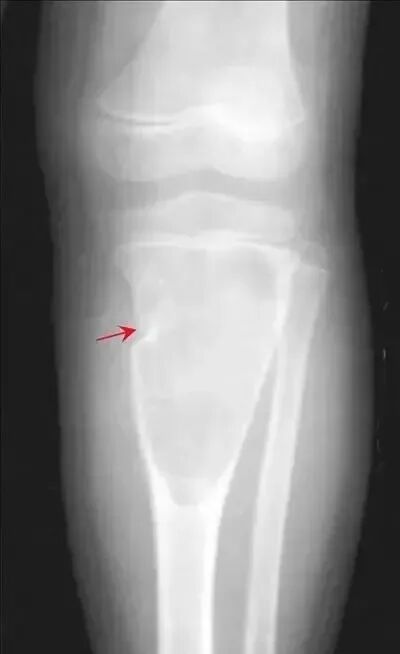

【普通放射图片】:

【影像表现】:A:外伤致骨化性肌炎,胫骨内侧上段软组织内可见钙化灶(↑),B:左腋下淋巴结钙化,左侧腋下软组织内见条状钙化灶。

【影像诊断】:软组织钙化(外伤致骨化性肌炎)的X线表现。